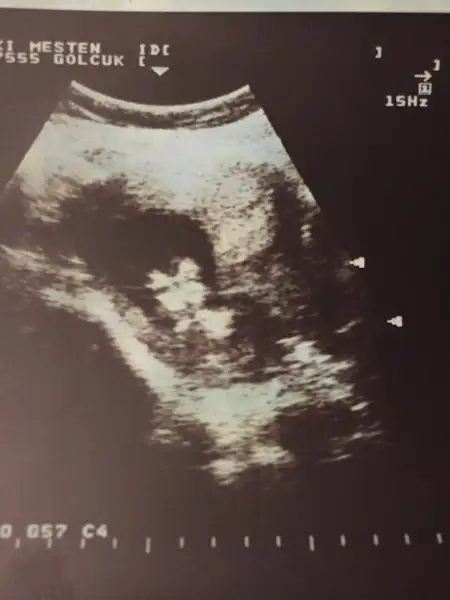

Kızlar ilk oğlumun usg lerini buldum fikir olsun diye paylaşıyorum tüm yüz hatları ağız dudak çene göz çukurları bile belli gerçekten erkek bebekler daha belirgin oluyor sanırım yinede usg cihazından olabilir bilmiyorum bu usg 9 sene öncesi